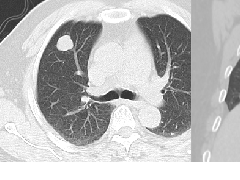

肺转移瘤的十种不典型CT表现  肺内淋巴结的CT表现特点及与病理对照